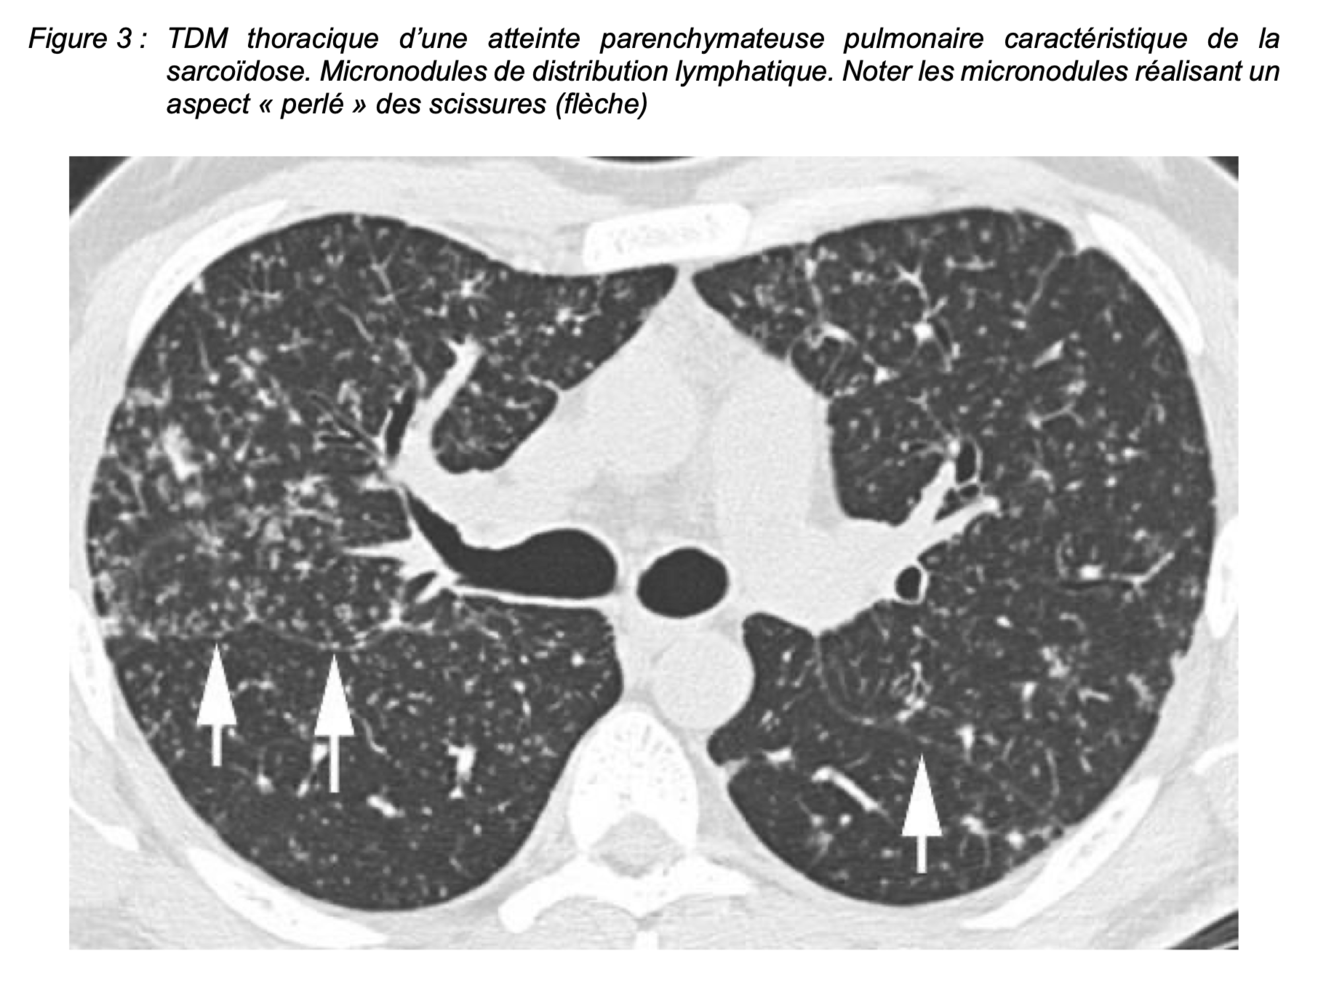

Signes au TDM de sarcoidose :

▪ des micronodules, confluents, bilatéraux,

▪ prédomine dans la moitié supérieure des poumons selon une distribution lymphatique c’est-à-dire le long des axes péribroncho-vasculaires qui sont épaissis et les zones sous-pleurales, y compris le long des scissures (Figure 3),

▪ à l’échelle du lobule pulmonaire, ils prédominent dans la zone péri-lobulaire et peuvent s’accompagner de réticulations septales.

=> Figure 3